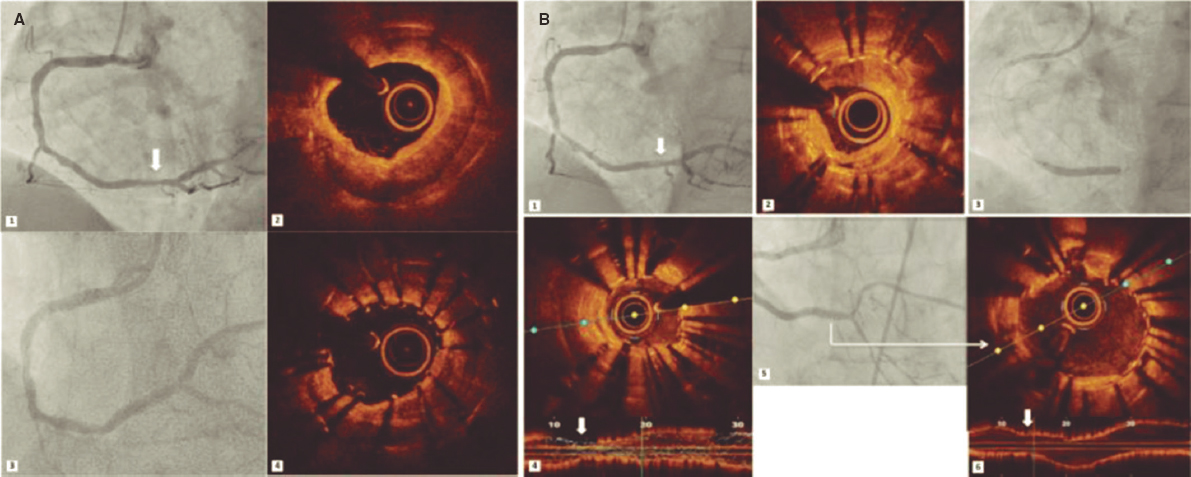

CASE RESOLUTION

The evolution of the patient was not favorable, brain death was declared 24 h after admission, and the patient was eventually declared dead. The microscopic analysis of the coronary aspirate revealed the presence of mesenchymal tissue with myxoid changes consistent with tumor embolism (figure 1) whereas the macroscopic piece confirmed the diagnosis of atrial myxoma (figure 2, arrow).

Figure 1. The red arrows point at the fibrinoid tissue. The blue arrows point at the mesenchymal tissue with myxoid changes.

Although they are regarded as benign tumors, cardiac myxomas can lead to life-threatening events. Among their different ways of presentation, coronary embolism is one of the least common of all (0.06%). One possible explanation to this low incidence can be found in the anatomical-functional characteristics such as the existing straight angles between the aortic root and the coronary ostia, the protection of coronary arteries by the cusps of the aortic valve, and the coronary filling during ventricular diastole.

The shape of the tumors is one of the leading predictors of embolization, and papillary or villous myxomas are thought to have the highest potential to cause embolisms. According to the medical literature available, the right coronary artery is the most common location of embolization; however, there is an interesting percentage of normal coronary arteries on the angiography1 probably attributed to the fact that the myxomatous histology of the tumor favors greater fragmentation, distal spread, and spontaneous resolution. The clinical signs of tumor embolism go from silent events to ST-segment elevation acute myocardial infarctions (STEMI) complicated with cardiogenic shock, as it was our case, and the emergent therapy here is similar to the management of atherosclerotic coronary syndromes.